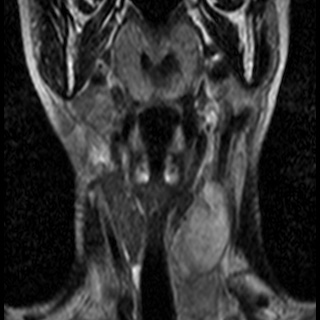

Невринома множественная шейного отдела с врастанием в спинно-мозговой канал

Здравствуйте! Мне 27 лет. Я стала жаловаться на головокружение, головные боли, пульсирование в голове. После исследования мрт выявилась следующая патология . Документы предоставляю. Можете ли Вы помочь в этой патологии? Как попасть к Вам на консультацию, учитывая эпидемиологическую обстановку? Спасибо.